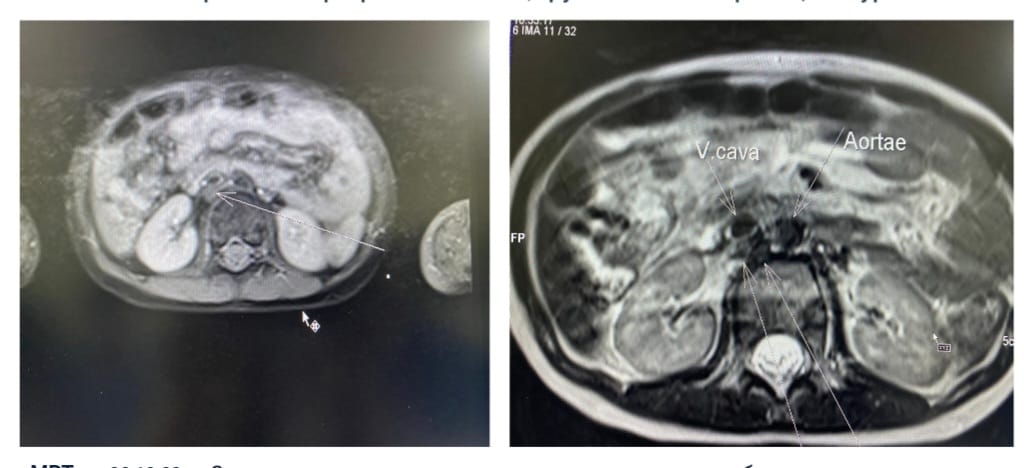

Нейробластома - это эмбриональная опухоль симпатической нервной системы, которая характеризуется агрессивным неуправляемым ростом и бурным метастазированием. Не смотря на разработанные схемы терапии прогноз для больных группы высокого риска остаётся неблагоприятным. Одним из достижений в лечении нейробластомы группы высокого риска является иммунотерапия с применением динутуксимаба бета (Карзиба), который позволяет повысить шансы на выздоровление данным пациентам. Однако применение Карзибы до недавнего времени не представлялось возможным ввиду его высокой стоимости и отсутствия регистрации.